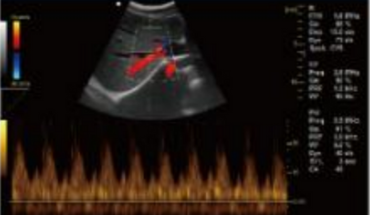

- B+CF/DPDI+PW (Triplex)